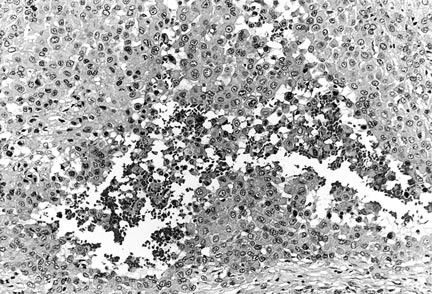

Histologically, 12 tumors (60%) were classified as the large-cell subtype, 6 (30%) as the conventional subtype, and 2 (10%) as the angiomatoid subtype (Table 3). The large-cell epithelioid sarcomas were characterized by sheets of large, rounded polygonal or short spindle cells with enlarged vesicular nuclei, prominent, central single nucleoli and abundant amphophilic cytoplasm (Fig. 2). Rhabdoid cells containing intracytoplasmic, paranuclear hyaline inclusions were abundant in 10 tumors of the large-cell subtype, in three tumors of the conventional subtype, and in one of the angiomatoid subtype. Conventional epithelioid sarcomas displayed nodules of a mixture of atypical spindle and epithelioid cells bordering central areas of hyalinization and necrosis (Fig. 3). Angiomatoid tumors had cystic, blood-filled pseudovascular spaces bordered by epithelioid and spindle cells, similar to those seen in typical cases (Fig. 4).